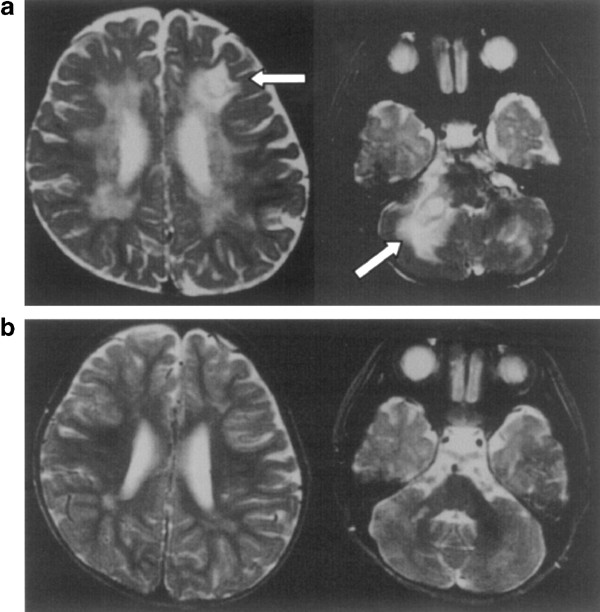

Despite this recipient-dominant bone marrow recovery, clinical manifestations have improved markedly. No new signs of AP have occurred and neurological development is progressing satisfactorily. Some examinations also corroborate neurological improvement, with MRI showing diminishing infiltration of the CNS (Figure 2), and decreasing cell counts as well as neopterin level in the CSF. Regarding hematological and immunological parameters, neutropenia persists at approximately 500×106/l and cells still contain Chediak–Higashi granules. Peripheral blood T- and B-cell populations are nearly normal with normal antigen-specific responses (data not shown). NK cell activity is low but nearly normalized and stable at 12%, which is much better than pre-BMT (3%).